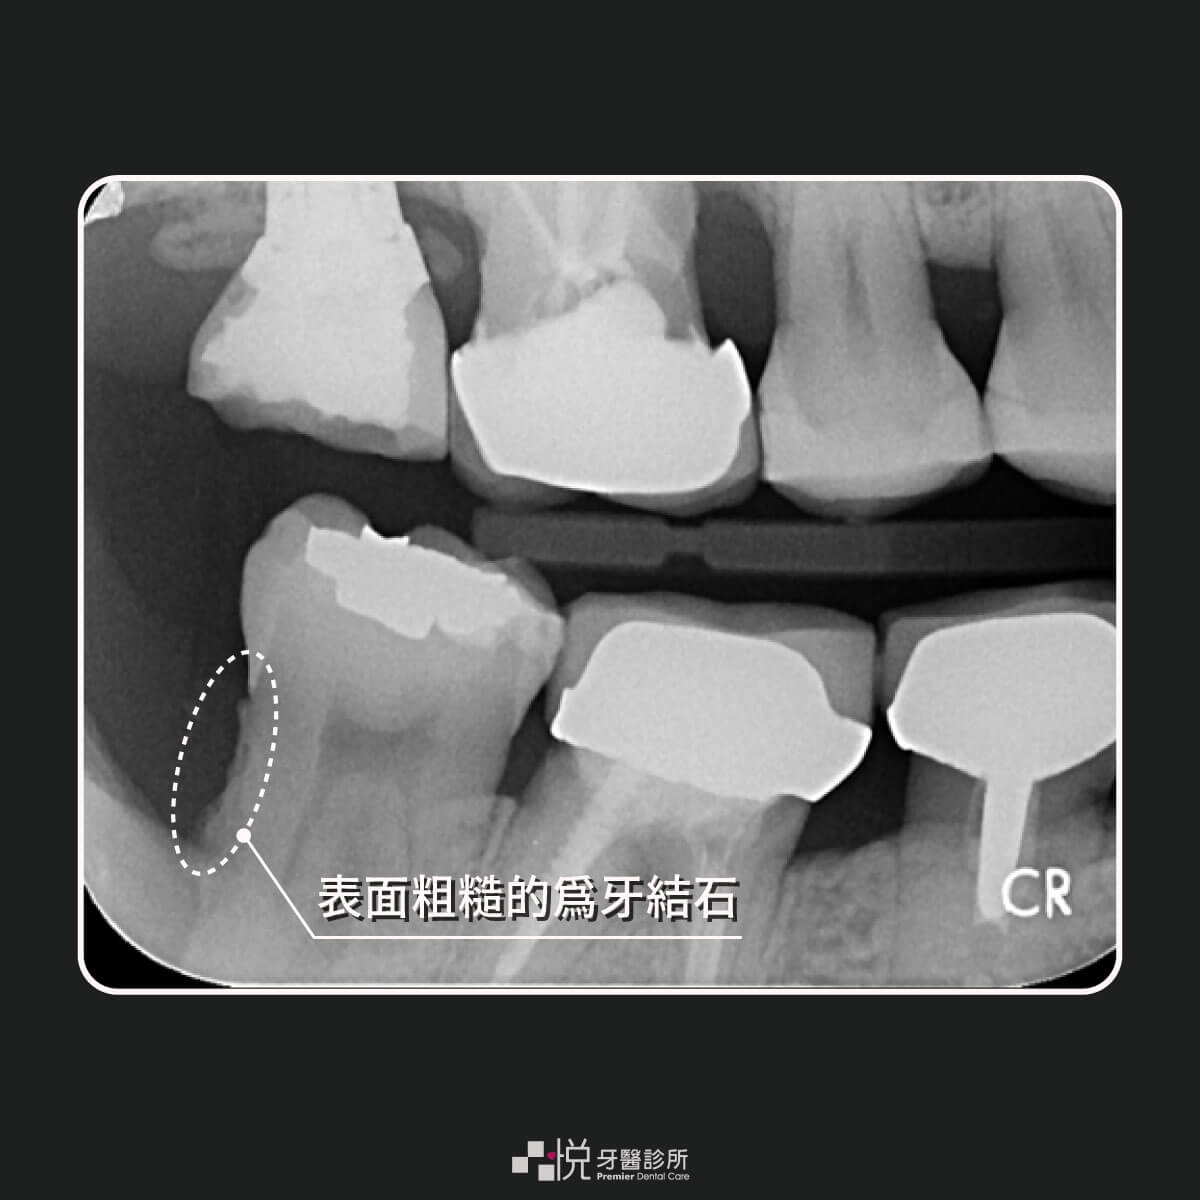

牙周治療說穿了,就是把牙根表面的牙結石以及牙菌斑用治療器械清乾淨的動作。附著在牙根的牙結石與細菌是牙周發炎的元兇,牙周治療就是把這些髒物去除的過程。

牙周病較嚴重時牙結石卡的位置較深,如術前檢查發現無法用我們牙周治療器械清除時,可能要考慮用手術方式去除。

但有了雷射之後,過去這些傳統非手術治療無法清潔的結石,現在可以用非手術搭配雷射的方式以微創的方式清除!

而說起水雷射我們就可以直接作用在牙結石,使用水雷射激化的水滴可以直接把牙結石清除掉,因此在治療可以更微創、更徹底。

那為什麼會需要更久的時間呢?因為使用雷射做牙周治療也就代表我們看得更清楚,以及可以清的更深,自然而然跟傳統牙周治療相比要清的牙根表面的牙結石量增加!要清除的牙結石的量與範圍增加,因此操作時間也變長。

由於我們使用水雷射可以清的更深、更徹底,所以會讓治療時的醫師操作視野變更良好。牙科治療如外科手術,每項治療都是醫師親手操作的,因此可以遵循外科手術的基本原則,也就是「你看得到,你就做得到」。

牙周治療也是如此,如果操作的視野不好其實我們真的很難把牙根周邊的牙結石及牙菌斑清乾淨(如上圖),幸好有雷射的應用,我們可以更微創且更徹底把牙根表面的牙結石清乾淨!